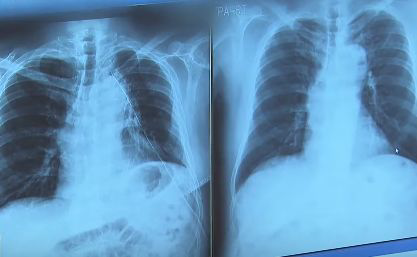

폐암초기증상 허리 통증

허리 통증은 폐암과 관련 있다는 연구보고가 나왔습니다. 만약 담배를 오래 피우신 분이라면 자신의 몸에 통증이 없는지 살펴보고 만약 허리 통증이 심하다면 병원에 내원해 정밀 검사받는 것을 추천드립니다.

본문에서는 폐암 초기 증상과 허리 통증과의 연광성을 자세히 다루려고 합니다. 분문 끝까지 읽어주시기 바랍니다.

허리 통증이 폐암의 증상인 경우에는 다른 통증과 구분되는 무언가가 있습니다. 폐암으로 인한 허리 통증은 폐암 환자의 약 25% 정도가 겪는 통증입니다.